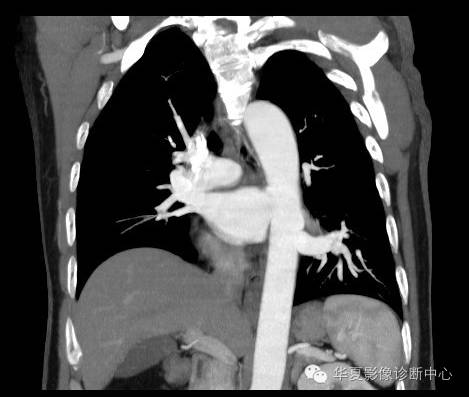

| 影像表现及分析: | 影像表现:定位左下叶;左下叶体积缩小,整体密度增高,支气管分布正常,其内见血管增多,但是走形正常,未见杂乱、迂曲的血管影;血管连向肺门下方软组织密度结节灶,结节与主动脉分界不清,增强后,见降主动脉发出异常粗大血管供血整个左下叶,左下肺动脉细小。 |

| 确诊依据: | CTA明确左下叶供血动脉为降主动脉发出 |

异常体动脉供应正常下肺基底段完整含义为起源于降主动脉的异常动脉供应下肺基底段,而基底段支气管树和肺实质正常,同时基底段肺动脉缺如或狭窄【大部分缺如(完全型),部分狭窄(不完全型)】;95%以上累及左下肺,因此也称为异常体动脉供应正常左下肺基底段。 病因尚未明确,可能是胚胎发育时期供应肺芽的背主动脉原始小分支退化不全,与肺实质形成异常连接,并影响肺动脉与肺血管床连接而导致此部位肺动脉发育不良,而支气管、肺组织的发育未受影响。本病的病理生理基础为左向左的分流,体动脉供应的肺组织充血,体循环的高压可增加肺血管床的压力和左心负荷,同时也增加肺循环量和压力而增加右心负荷,导致各种临床症群。本病可无临床症状,部分患者可有咯血、呼吸道感染、呼吸困难、充血性心力衰竭。 影像表现:左肺下叶体积缩小,整体密度稍增高,支气管树走形、分布正常,血管增多、稍增粗;增强后显示左下肺动脉幼小,甚至不发育;下叶由主动脉发出的粗大血管供血。 |